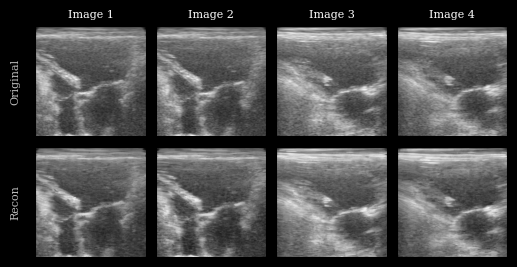

Visualization

We plot the original images and reconstructions for comparison.

Encode and Decode

We encode and decode the images using the autoencoder. TAESD expects grayscale or RGB, so we keep the input as is.

mse = ops.convert_to_numpy(ops.mean((recon - batch) ** 2))

MSE (reconstruction): 0.009169135